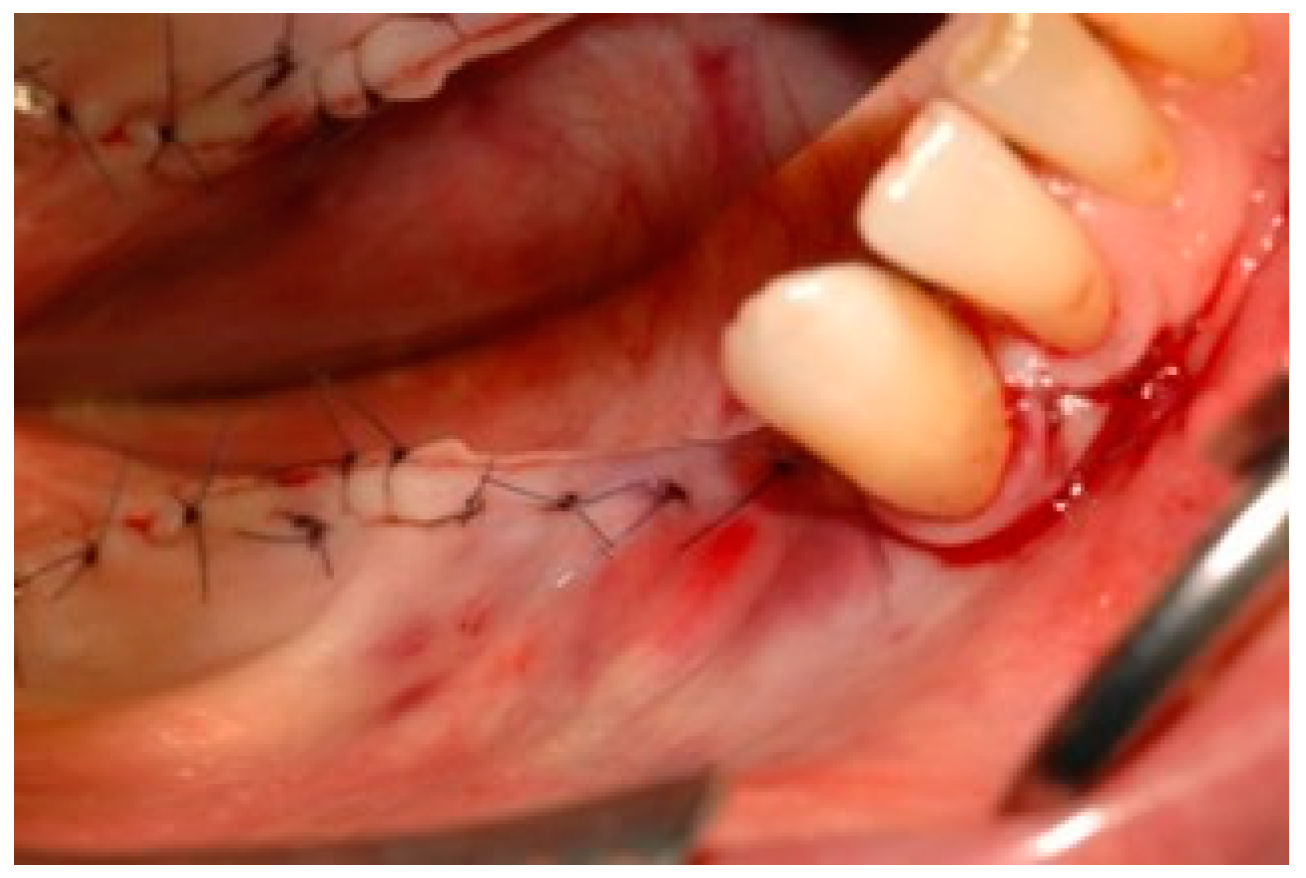

2. Case Description